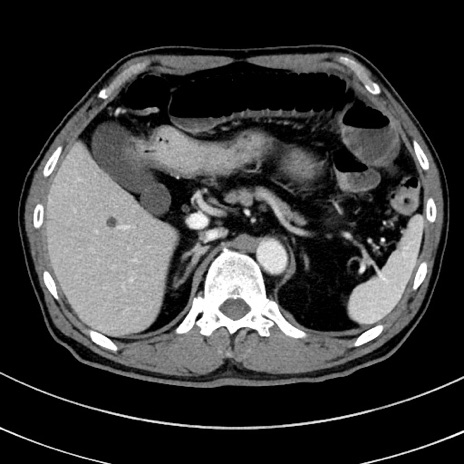

症例8(横断像)

【症例】 60歳代男性

【主訴】 黒色吐物

【現病歴】 4日前から嘔気自覚、2日前の朝食後にも嘔気あり、自分で手で嘔吐反射起こし嘔吐したところ血が混ざっていたため受診。

【既往歴】 5年前汎発性腹膜炎を伴う急性虫垂炎で手術、高血圧、前立腺肥大症、高脂血症

【身体所見】 腹部正中に手術癩痕あり 腹部平坦・軟圧痛なし膨満感あり

【データ】WBC 8400、CRP 4.54